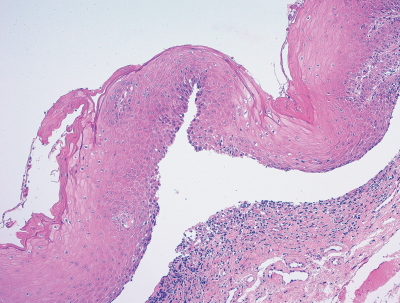

38歳の女性。歯肉の接触痛を主訴として来院した。3か月前から歯肉に水疱ができて、すぐに潰れしみるようになり、次第に口腔内全体がヒリヒリ痛むようになったという。初診時の口腔内写真と生検時のH-E染色病理組織像を別に示す。

BP180 類天疱瘡

デスモグレイン 尋常性天疱瘡